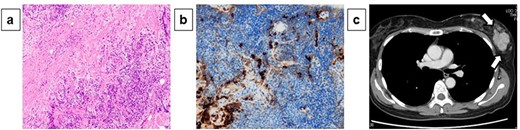

A 54-year-old woman presented with a tumor in her left breast. The patient had no relevant medical or family history. During physical examination, an elastic hard mass measuring ~6 cm in size was palpated in the upper-outer area of the left breast (Fig. 1a). An induration of ~4 cm was also found on the right cheek (Fig. 1b). Mammary ultrasonography revealed an irregular hypoechoic tumor of measuring 45.0 × 43.0 × 32.0 mm in size in the upper-outer quadrant of the left breast (Fig. 1c). Core-needle biopsy performed in the same site revealed a high degree of mixed T and B lymphocytic and plasma cell infiltration, as well as interstitial fibrosis (Fig. 2a). Many plasma cells were IgG positive, of which >40% were IgG4 positive (Fig. 2b). These biopsy findings led to a diagnosis of IgG4-RM of the left breast. Computed tomography exhibited no significant findings besides the left mammary mass and left axillary swelling (Fig. 2c). IgG4-RD was diagnosed based on hematological examination results revealing elevated serum IgG4 levels (332 mg/dl). Based on comprehensive diagnostic criteria for IgG4-RDs, we diagnosed the patient with IgG4-RM. The condition was treated with prednisolone (30 mg/day, 0.6 mg/kg/day) for 4 weeks, which resulted in a decrease in the tumor size. The patient is currently being followed up with maintenance therapy.

Physical examination and ultrasonography findings: During physical examination, an elastic hard mass measuring ~6 cm in size was palpated in the upper-outer area of the left breast (a). An induration of ~4 cm was also found on the right cheek (b). Mammary ultrasonography revealed an irregular hypoechoic tumor of measuring 45.0 × 43.0 × 32.0 mm in size in the upper-outer quadrant of the left breast (c).